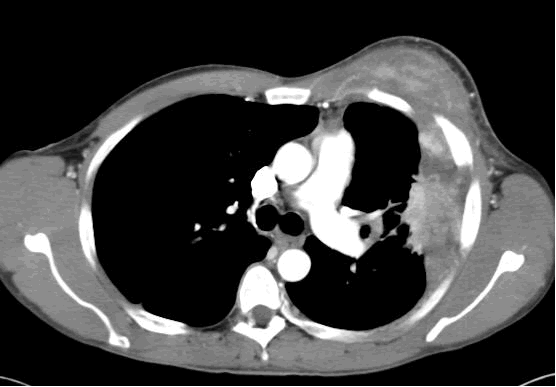

| Figure 1: PA chest film reveals a left pleural-based mass with pleural thickening and upper lobe scarring. |

PA and lateral chest film revealed patchy consolidation of the left lung with a large pleural-based mass, left apical pleural thickening, and right upper lobe scarring (Figure 1). Helical CT scan of the chest, abdomen, and pelvis with contrast demonstrates a large, 10.8 x 4.1 cm left pleural-based mass extending into the chest wall and left breast (Figure 2). There was periosteal thickening and irregularity of adjacent ribs. Multiple enlarged mediastinal, left hilar, and supraclavicular nodes were noted, the largest 1.5 x 2.6 cm in the AP window or station five region. There was patchy consolidation of the left and right upper lobes. An MRI of the thorax with contrast was obtained and confirmed the presence of left supraclavicular adenopathy and an enhancing mass with extension into the chest wall involving the ribs, infiltration of the pectoralis muscle, and extension into the left lung parenchyma. The main differential diagnoses at this time were neoplasm (sarcoma, advanced lung cancer, mesothelioma, lymphoma, osteosarcoma).